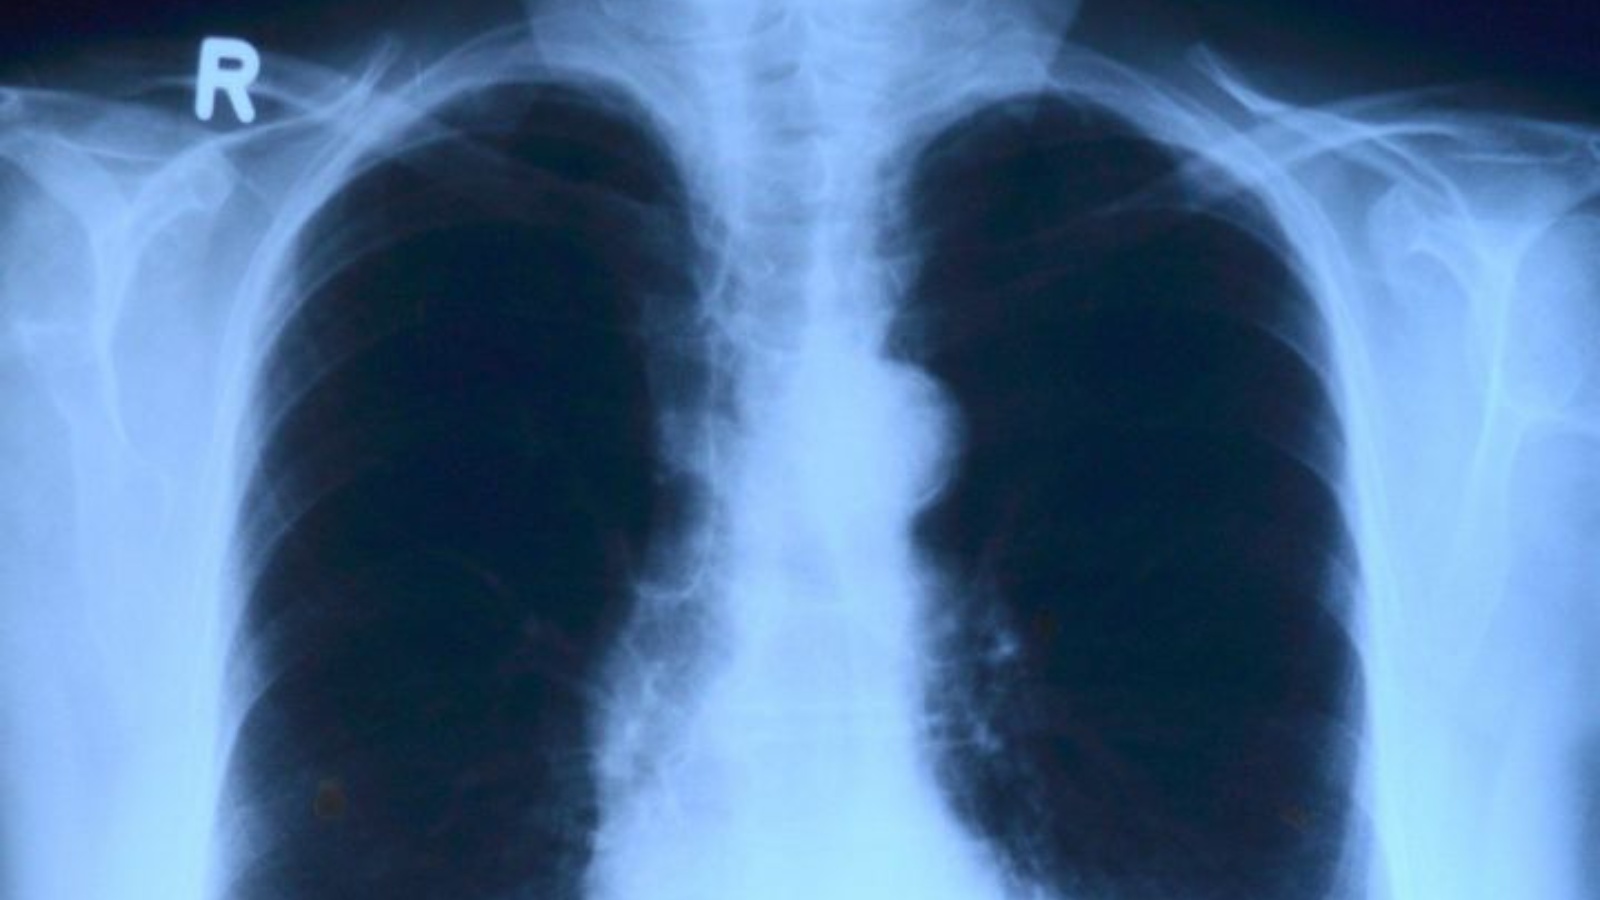

С 21 по 30 марта в Татарстане, в том числе Ютазинском районе проходит декадник «Профилактика туберкулеза»

Приуроченное ко Всемирному дню борьбы с туберкулезом.

По данным, предоставленным медсестрой кабинета фтизиатрии Уруссинской ЦРБ Валентиной Ахметшиной, в Ютазинском районе на учете с туберкулезом состоят 14 человек. В текущем году выявлен один человек с данным заболеванием. В 2021 году прошли флюорографическое обследование 10 210 ютазинцев.